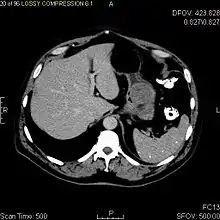

The purpose of radiologic imaging is to locate the lesion, evaluate for signs of invasion and detect metastasis. Features of GIST vary depending on tumor size and organ of origin. The diameter can range from a few millimeters to more than 30 cm. Larger tumors usually cause symptoms in contrast to those found incidentally which tend to be smaller and have better prognosis.[4][12] Large tumors tend to exhibit malignant behavior but small GISTs may also demonstrate clinically aggressive behavior.[13]

Preferred imaging modalities in the evaluation of GISTs are CT and MRI,[15]:20–21 and, in selected situations, endoscopic ultrasound. CT advantages include its ability to demonstrate evidence of nearby organ invasion, ascites, and metastases. The ability of MRI to produce images in multiple planes is helpful in determining the bowel as the organ of origin (which is difficult when the tumor is very large), facilitating diagnosis.

As the tumor grows it may project outside the bowel (exophytic growth) and/or inside the bowel (intraluminal growth), but they most commonly grow exophytically such that the bulk of the tumor projects into the abdominal cavity. If the tumor outstrips its blood supply, it can necrose internally, creating a central fluid-filled cavity with bleeding and cavitations that can eventually ulcerate and communicate into the lumen of the bowel. In that case, barium swallow may show an air, air-fluid levels or oral contrast media accumulation within these areas.[13][16] Mucosal ulcerations may also be present. In contrast enhanced CT images, large GISTs appear as heterogeneous masses due to areas of living tumor cells surrounding bleeding, necrosis or cysts, which is radiographically seen as a peripheral enhancement pattern with a low attenuation center.[12] In MRI studies, the degree of necrosis and bleeding affects the signal intensity pattern. Areas of bleeding within the tumor will vary its signal intensity depending on how long ago the bleeding occurred. The solid portions of the tumor are typically low signal intensity on T1-weighted images, are high signal intensity on T2-weighted images and enhance after administration of gadolinium. Signal-intensity voids are present if there is gas within areas of necrotic tumor.[14][17][18]

Malignancy is characterized by local invasion and metastases, usually to the liver, omentum and peritoneum. However, cases of metastases to bone, pleura, lungs and retroperitoneum have been seen. In distinction to gastric adenocarcinoma or gastric/small bowel lymphoma, malignant lymphadenopathy (swollen lymph nodes) is uncommon (<10%) and thus imaging usually shows absence of lymph node enlargement.[12] If metastases are not present, other radiologic features suggesting malignancy include: size (>5 cm), heterogeneous enhancement after contrast administration and ulcerations.[4][12][19] Also, overtly malignant behavior (in distinction to malignant potential of lesser degree) is less commonly seen in gastric tumors, with a ratio of behaviorally benign to overtly malignant of 3-5:1.[4] Even if radiographic malignant features are present, these findings may also represent other tumors and definitive diagnosis must be made immunochemically.